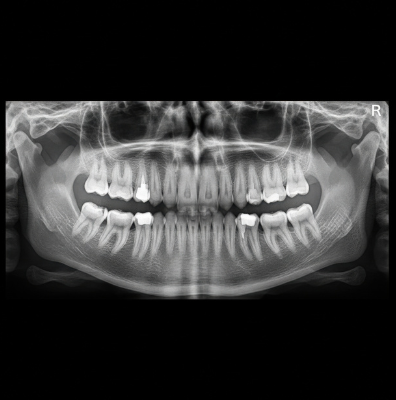

Here’s what 3D dental imaging shows us that traditional X-rays simply miss:

- The exact thickness and density of your jawbone before dental implants or bone grafting

- Hidden infections at the tip of a root that don’t show on flat films

- The precise location of the inferior alveolar nerve, which matters before wisdom tooth removal or surgical extractions

- Extra roots, curved roots, or calcified canals before root canal therapy

- How close your sinus floor sits to your upper teeth, which is critical for a sinus lift

What dental problems can a 3D scan find that a regular X-ray would miss?

A 3D scan finds fracture lines running down roots, infections hiding behind other teeth, and nerves too close to wisdom tooth roots. It also shows bone loss that’s just starting, extra or curved root canals, and how close your sinus floor sits to your upper teeth. These details change your treatment plan completely. Standard X-rays often show these areas as normal even when something serious is developing underneath.